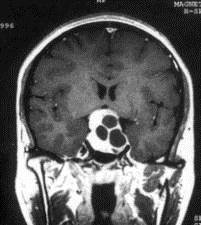

问题 病历摘要:??患者男性,35岁。性功能减退2年,视力下降6月。既往体健。体检:神清,皮肤细腻,毛发稀疏。视力左眼0.3,右眼0.5,双瞳等大等圆,直径3.5mm,对光反射稍迟钝,双颞侧偏盲,双眼底视神经乳头原发性萎缩,余神经系统未见异常。 患者出现上述情况,作何处理?提示:术后第?1日患者尿量300ml/小时,尿比重1.002